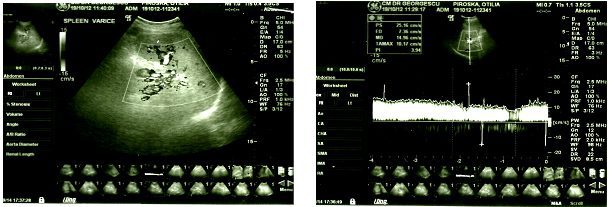

În figura de mai jos se remarcă dilatații ale VS în hilul splenic cu turbulențe în Doppler color și un aspect spectral de circulație portală cu scăderea IP al venei porte.

În figura alăturată, pacient cu creșterea IR = 0,56 la nivelul arterei hepatice în hil.